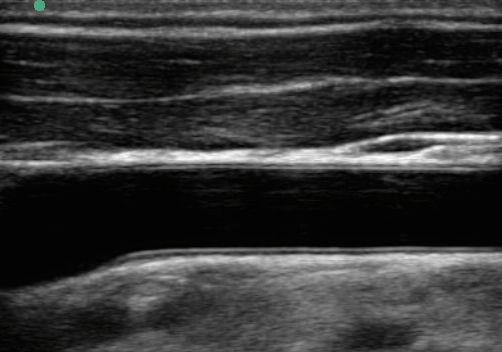

頸動脈 IMT画像

IMT - Intima-media Thickness